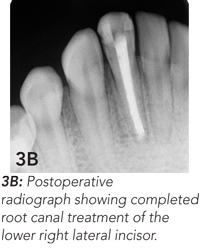

Endodontic treatment was begun, but, because of a dental phobia, the girl delayed completion of this treatment. She presented again 6 months later because the skin lesion had worsened, becoming raised, firm and erythematous (Figure 3A). Endodontic treatment was completed (Figure 3B), and the skin lesion began to heal. At 6-month follow-up, wound contracture had caused dimpling of the skin in the affected area (Figure 3C). This may require surgical revision.